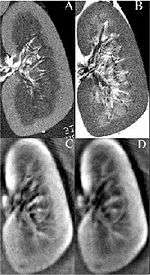

Fig. 1. First 3D thermoaoustic images of biologic tissue (lamb kidney)(C,D) in comparison to MRI images of the same kidney (A,B).

Thermoacoustic imaging was originally proposed by Theodore Bowen in 1981 as a strategy for studying the absorption properties of human tissue using virtually any kind of electromagnetic radiation.[1] But Alexander Graham Bell first reported the physical principle upon which thermoacoustic imaging is based a century earlier.[2] He observed that audible sound could be created by illuminating an intermittent beam of sunlight onto a rubber sheet. Shortly after Bowen's work was published, other researchers proposed methodology for thermoacoustic imaging using microwaves.[3] In 1994 researchers used an infrared laser to produce the first thermoacoustic images of near-infrared optical absorption in a tissue-mimicking phantom, albeit in two dimensions (2D).[4] In 1995 other researchers formulated a general reconstruction algorithm by which 2D thermoacoustic images could be computed from their "projections," i.e. thermoacoustic computed tomography (TCT).[5] By 1998 researchers at Indiana University Medical Center extended TCT to 3D and employed pulsed microwaves to produce the first fully three-dimensional (3D) thermoacoustic images of biologic tissue [an excised lamb kidney (Fig. 1)].[6] The following year they created the first fully 3D thermoaocustic images of cancer in the human breast, again using pulsed microwaves (Fig. 2).[7] Since that time, thermoacoustic imaging has gained widespread popularity in research institutions worldwide.[8] As of 2008, three companies were developing commercial thermoacoustic imaging systems - Seno Medical, Endra, Inc. and OptoSonics, Inc.